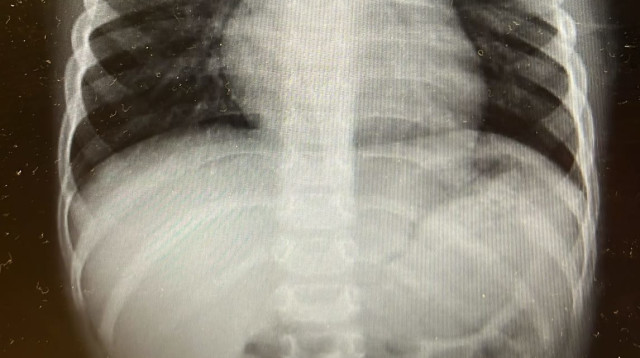

הסיוט של כל הורה - הפעם נגמר בנס גדול: "זה מצב חירום, מדובר באזור רגיש"